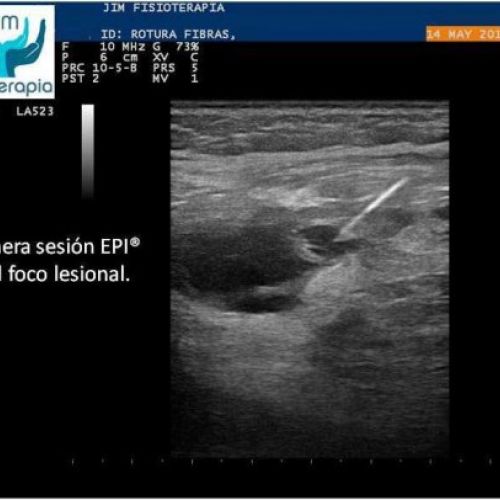

Tratamiento de rotura muscular con EPI®

Terapia de EPI® para el tratamiento de rotura muscular. Caso clínico de JIM Fisioterapia.